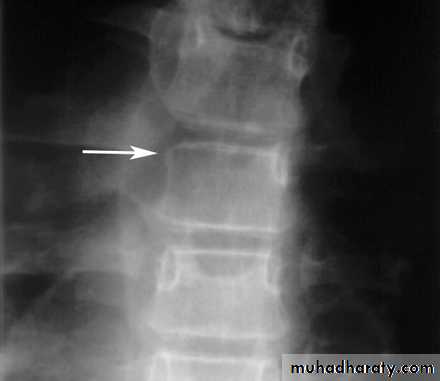

Wedge fracture

Burst fracture